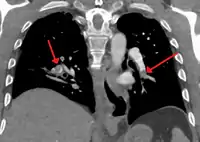

CT pulmonary angiography

CT pulmonary angiography (CTPA) is a pulmonary angiogram obtained using computed tomography (CT) with radiocontrast rather than right heart catheterization. Its advantages are that it is accurate, it is non-invasive, it is more often available, and it may identifying other lung disorders in case there is no pulmonary embolism. The accuracy and non-invasive nature of CTPA also make it advantageous for people who are pregnant.[58]

On CT scan, pulmonary emboli can be classified according to the level along the arterial tree.

Segmental and subsegmental pulmonary emboli on both sides

CT pulmonary angiography showing a "saddle embolus" at the bifurcation of the main pulmonary artery and thrombus burden in the lobar arteries on both sides.